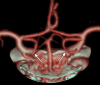

A 71-year-old lady presented with a symptomatic left cerebral occipital lobe infarct. With a history of paroxysmal atrial fibrillation a cardioembolic source was initially postulated. Prior significant bleeding while anticoagulated precluded warfarin therapy. Further investigations revealed a critical left internal carotid stenosis with a persistent fetal origin of the left posterior cerebral artery. She was successfully treated surgically and suffered no further ischaemic events. Physicians encountering posterior circulation stroke should be aware of this potentially treatable important diagnosis.

- De Monye C, Dippel DW, Siepman TA, et al. Is a fetal origin of the posterior cerebral artery a risk factor for TIA or ischemic stroke? A study with 16-multidetector-row CT angiography. J Neurol 2008;2013:239–45 - PubMed

- Jongen JC, Franke CL, Ramos LM, et al. Direction of flow in posterior communicating artery on magnetic resonance angiography in patients with occipital lobe infarcts. Stroke 2004;2013:104–8 - PubMed